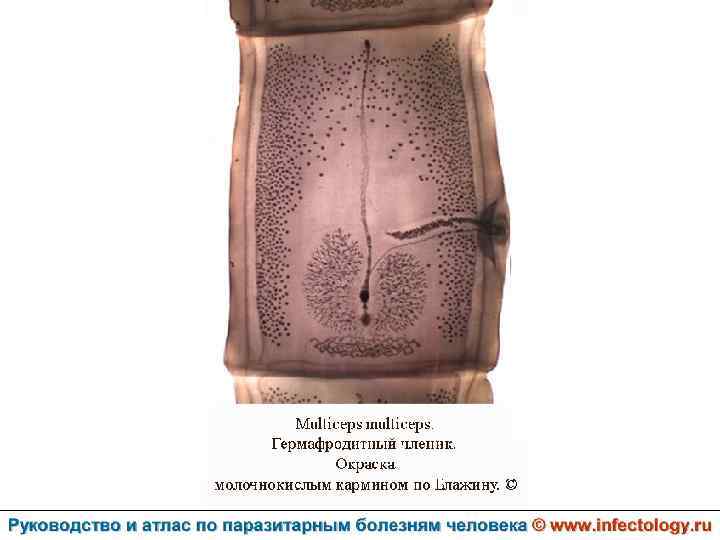

Ценуроз (шифр по МКБ 10 – B 71. 8)– спорадически встречающееся заболевание человека, вызываемое личиночной формой (ценуром) гельминтов рода Multiceps, половозрелые формы которых паразитируют у собак и диких волчьих. . Проявляется разнообразными клиническими симптомами в зависимости от вида паразита.